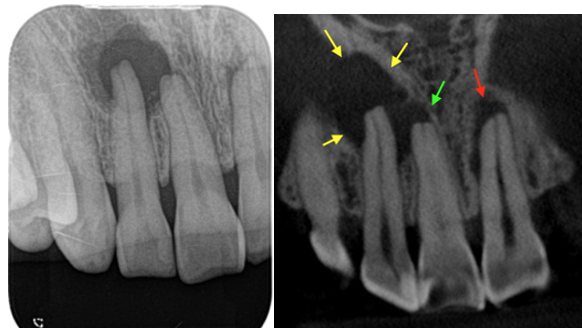

奥歯の歯茎が腫れている

上顎の奥歯、第一大臼歯(6番)は三又の根っこをしています。そのうちの一本(近心頬側根といいます)は複雑な形をしています。 MB2と言われる4つめの根管があることが多く、またない場合でも根管の形がとても複雑です。MB1とMB2の間にイスムスと言われる殺菌が届かない繋ぎ目があることも多く、殺菌が届かない部位に細菌がこびりついていると、MB2をしっかり処理して殺菌しても治らない場合があります。そうなったらいくら根管治療をしても殺菌が届きませんので、効果がなく、外科治療でその部分を処置するか、歯ごと抜歯して取り除く以外に方法がありません。今回の歯はCBCTで未処置のMB2が見つかり、MB2の殺菌処置を行いましたが術後1ヶ月半で腫れが再発、歯根端切除術を行いました。歯根を切断して観察すると感染源となっているイスムスがあり、削り取って逆充填処置を行い治癒に導いたケースです。

• 術前のCBCT画像、右上6の近心頬側根に透過像(炎症の黒い影)と未処置の根管MB2(赤色矢印)が見られ腫れている原因となっていることがわかる。

• 治療時画像、赤矢印部がMB2未処置、この部分を拡大殺菌していく。

• 治療時画像、MB2を拡大殺菌し、根管充填を行ったところ(緑矢印)。未処置部分の殺菌で治る歯が大多数です。

• 根管治療後一旦腫れが引いたものの、1ヶ月半で再発し歯根端切除術を行うこととなりました。術後のCBCTでは未処置だったMB2に根管充填がなされて殺菌できていることがわかります(緑矢印)。

• 再根管治療時に殺菌、根管充填したMB2を確認(緑矢印)。

• 青色の細菌の染め出し液で感染源のイスムスが発覚(青矢印)。根管治療で殺菌が届かない場所です。

• イスムスを削除しながら逆根管形成を行い、お薬(バイオセラミックパテ)を充填したところ(黄色矢印)。

• 歯根端切除前と術後半年のCBCT画像、感染源を除去してしっかり封鎖したことで、骨の再生を認め治癒が確認されました(黄色矢印)。